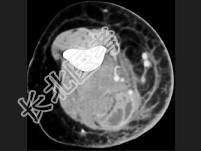

- 单项选择题男,26岁, 肘部红、肿、热、痛,疼痛呈搏动感, 结合图像,最可能的诊断是 ( )

A、脂肪瘤

B、脂肪肉瘤

C、软组织脓肿

D、血管瘤

E、淋巴管瘤